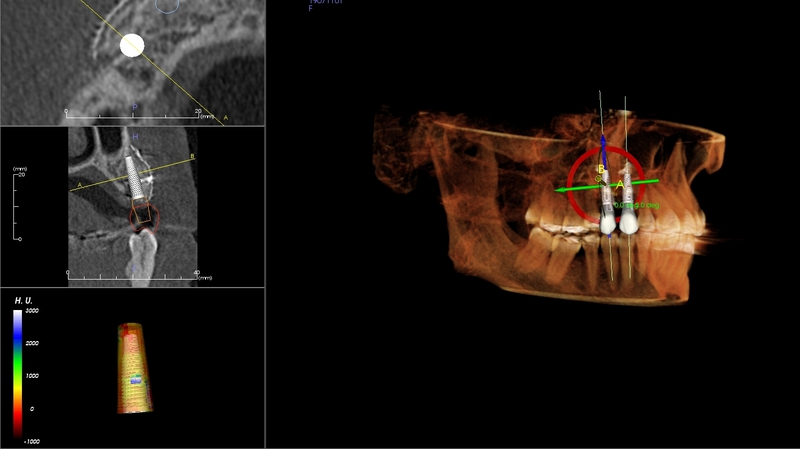

CT Scanner for Optimal Treatment Planning

New iCAT CT scanner offers precise imaging with radiation comparable to traditional x-ray units.  Using this 3D imaging technology the doctor can accurately plan surgery, avoid complications, and create custom implant treament plans.

The CT scanner's imaging allows us to create custom made surgical guides specific to each patient.  These surgical guides allow the precise placement of dental implants for optimal functional and esthetic results.

CT Guided Custom Implant Placment